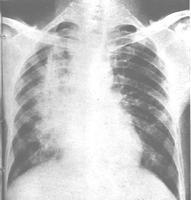

放射性肺炎是怎么回事?什么是放射性肺炎?放射性肺炎系由于肺癌、乳腺癌、食管癌、恶性淋巴瘤或胸部其他恶性肿瘤经放射治疗后,在放射野内的正常肺组织受到损伤而引起的炎症反应。轻者无症状,炎症可自行消散;重者肺脏发生广泛纤维化,导致呼吸功能损害,甚致呼吸衰竭。[1]